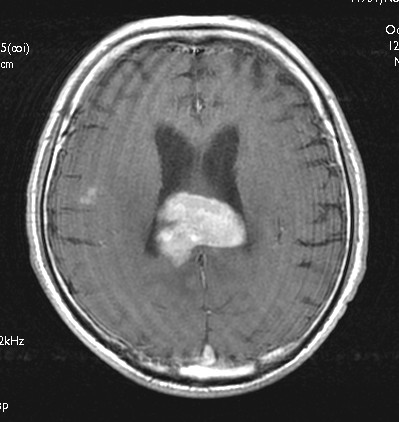

神経膠芽腫(glioblastoma) CE_T1W1_axi_1 CE_T1W1_axi_2  CE_T1W1_sag_1  CE_T1W1_cor_1  DWI_1  DWI_2